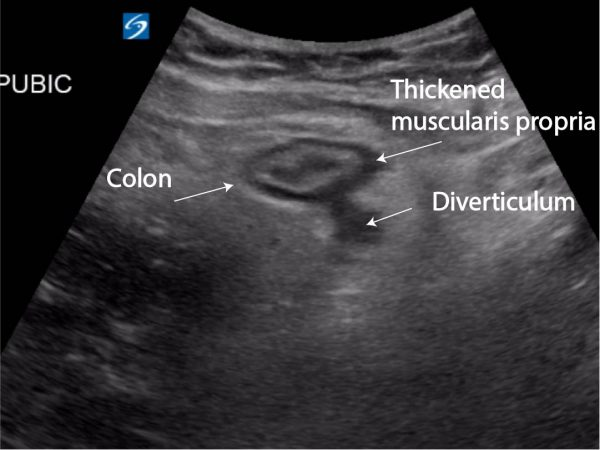

Sigmoid colon and hyperechoic pericolic fat surrounding diverticulum

General consensus criteria for positive diagnosis

- Diverticula: hypoechoic domed structure extending off of the colon

- Bowel wall edema >4- 5 mm surrounding a diverticula

- Enhancement/inflammation of pericolonic fat

- Sonographic tenderness to palpation